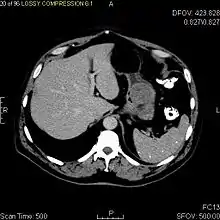

Non-enhanced CT image of a small GIST in the posterior stomach wall (arrow). The lesion appears subserosal. Incidental finding.

Small GISTs

Since GISTs arise from the bowel layer called muscularis propria (which is deeper to the mucosa and submucosa from a luminal perspective), small GIST imaging usually suggest a submucosal process or a mass within the bowel wall. In barium swallow studies, these GISTs most commonly present with smooth borders forming right or obtuse angles with the nearby bowel wall, as seen with any other intramural mass. The mucosal surface is usually intact except for areas of ulceration, which are generally present in 50% of GISTs. Ulcerations fill with barium causing a bull's eye or target lesion appearance. In contrast-enhanced CT, small GISTs are seen as smooth, sharply defined intramural masses with homogeneous attenuation.